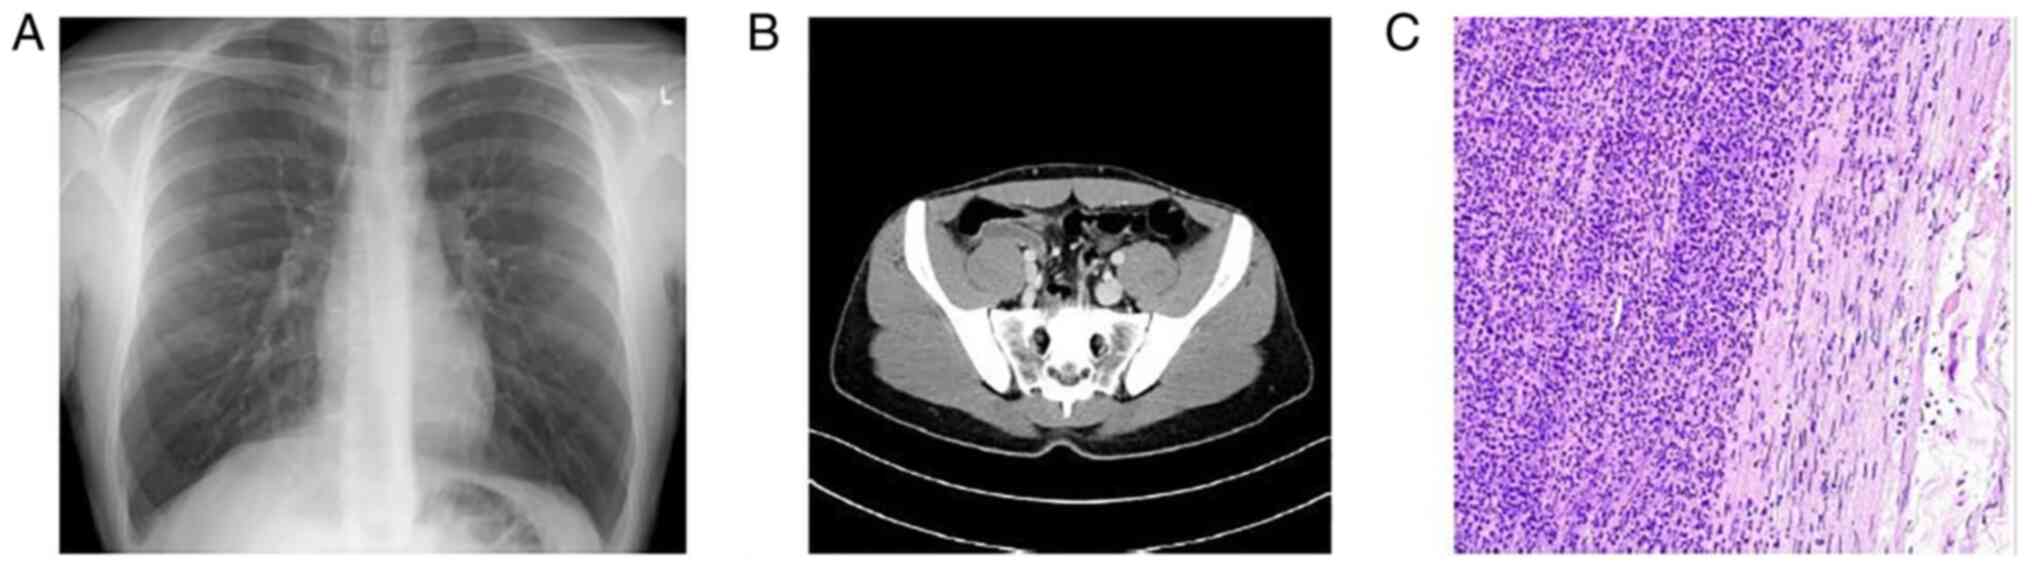

Figure 3

Case 3. (A) Normal chest X-ray. (B) An abdominal computed tomography revealed an enlarged appendix, ~12 mm in diameter, with significant wall thickening and stranding of the surrounding fat. (C) Hematoxylin and eosin staining; original magnification, x40. The histological analysis revealed acute appendicitis with a heavily inflamed mucosa with accompanying extensive ulceration and hemorrhage, covered by fibrinopurulent exudate.

A chest X-ray was performed, which was normal (Fig. 3A). The Alvarado total score was 6 out of 10 based on the symptoms and laboratory tests. The patient had possible appendicitis according to the Alvarado score. The patient underwent an abdominal CT scan, which revealed an enlarged appendix, with marked wall thickening and stranding of the surrounding fat (Fig. 3B). RT-PCR analysis for COVID-19 was conducted and the result was positive. With all COVID-19 precautions taken, a laparoscopic appendectomy was conducted under general anesthesia. The histopathological examination of appendicular tissue revealed acute appendicitis with heavily inflamed mucosa, with accompanying extensive ulceration and hemorrhage (Fig. 3C).